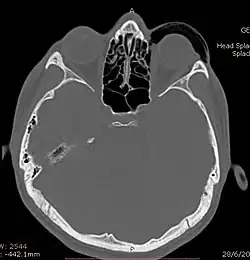

![]() | |

| Woman with preorbital swelling in orbital emphysema shown in CT scans | |

Computed tomography (CT)

Computed tomography is effective and sensitive in the diagnosis of orbital emphysema,[3][37] as it can confirm the anatomical location and size of air, bony defects, indentation of the eyeball, and the condition of the optic nerve, as well as the presence of any extraocular muscle entrapment and herniation of preorbital fat into the sinus cavities.[3][15][38] The location of the orbital emphysema is present near the site of the fracture.[1][3] The scans are usually taken along the transverse plane. Transverse images allow the evaluation of fractures in medial and lateral orbital walls. By reformatting these transverse images or taking coronal images, the examination of orbital floor and roof is permitted. Helical scanning is preferred as it has a lower imaging time and radiation dose comparing to conventional scanning, especially when reforming transverse helical scans into coronal images.[3] The staging of orbital emphysema can then be determined with visual acuity examination and ophthalmoscopy.[6] A disadvantage of using a CT scan is that when detecting air after orbital trauma, the presence of a wooden foreign object can give a false positive result of orbital emphysema. The wooden object can mimic the presence of orbital emphysema. Therefore, patients’ medical history is crucial in making the correct diagnosis.[3]